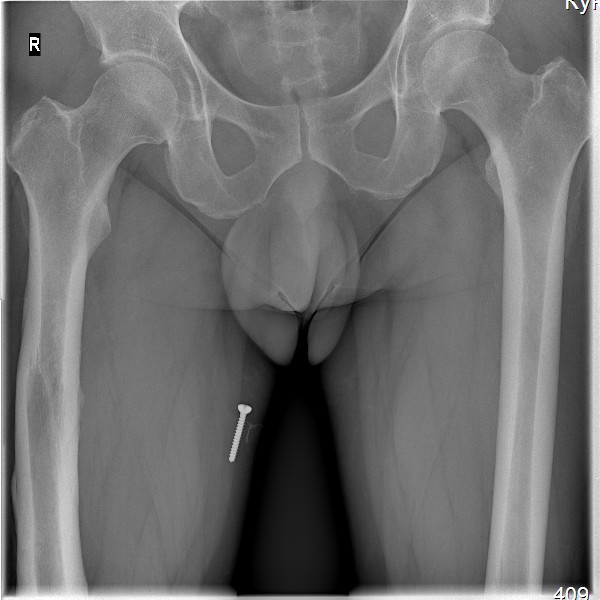

Пациент, мужчина, 45 лет. В 1982 году получил закрытый перелом диафиза бедренной кости справа. Результат консервативного лечения-варусная деформация бедренной кости В 1987 году выполнена вальгусная корригирующая остеотомия на уровне дистального эпифиза бедренной кости: варус бедренной кости нивелирован. Но в процессе лечения сформировалась выраженная контрактура в правом коленном суставе. Производилось 2 раза агрессивная разработка правого коленного сустава в аппарате типа Илизарова. В настоящее время беспокоят боли в области правого надколенника, при длительной ходьбе появляется ощущение скованности в 4-х главой мышце бедра, при отрыве правой стопы, голень и стопа как бы выбрасывается вперед (пациент, при этом, процесс разгибания в коленном суставе плохо контролирует). Правый коленный сустав внешне не деформирован, не отечен. Объем движений: сгибание до 90 градусов (до прямого угла, разгибание полное_180 гр. Сустав стабилен во всех плоскостях. Надколенник расположен практически на уровне суставной щели (тибиа-феморальной), малоподвижен, так называемая «игра надколенника» у пациента резко снижена . Пациент поступил в наше отделение для выполнения операции в объеме эндопротезирования правого коленного сустава. Однако, оценив коленный сустав, мы засомневались в необходимости данной операции этому пациенту. В данном случае , низкое стояние дегенеративно измененного правого надколенника нарушает функцию разгибательного аппарата правого коленного сустава и основная причина сосредоточена здесь, в надколеннике (по нашему мнению). У меня вопрос к коллегам: как деликатно, на нарушая разгибательный аппарат, помочь пациенту? Какие виды реконструктивных операции предпочтительны. С уважением Шушания Батал, ФБУ 3 ЦВКГ имени А А Вишневского

винт, видимый на рентгенснимках, фиксирован к коже пациента лейкопластырем при рентгенографии рентгенлабарантом, используется для калибровки рентегнснимка при планировании операции эндопротезирования.